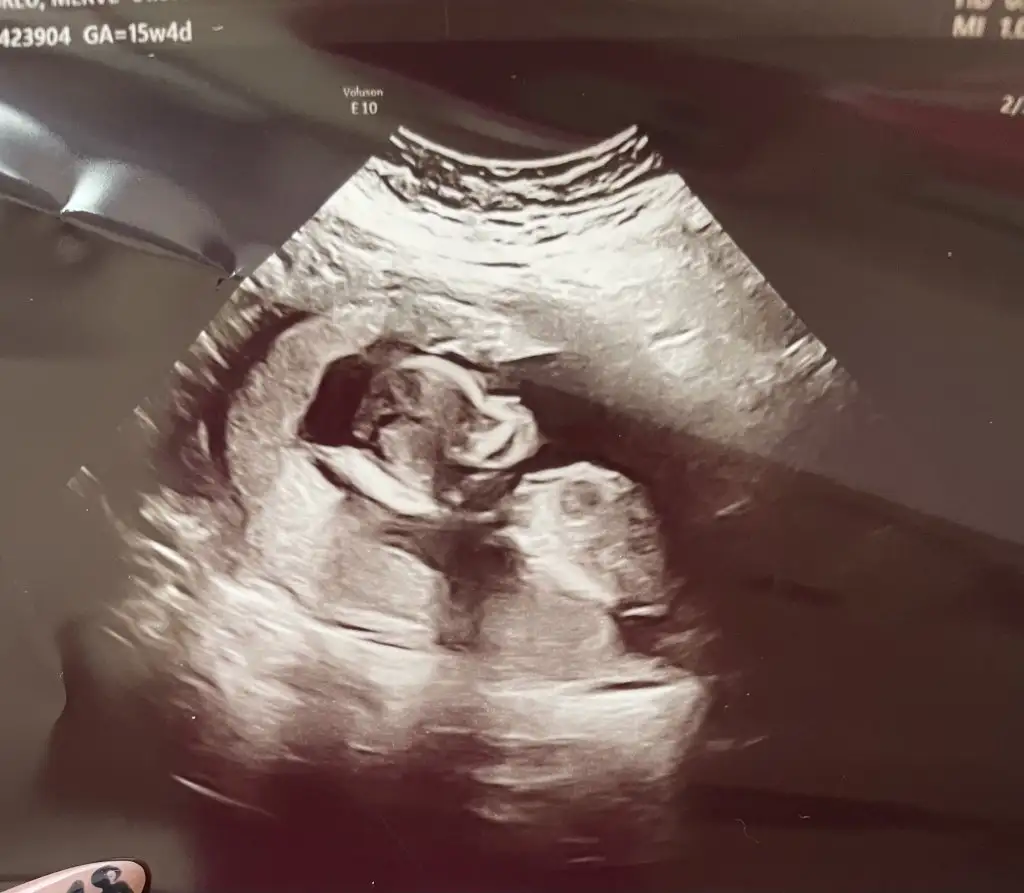

Selamlarrr, kontrolden çıktık, ikili test verdik. Ultrason detaylı bakıldı sağlıklı şimdilik kan verdik ama hâlâ cinsiyet net değil :110: